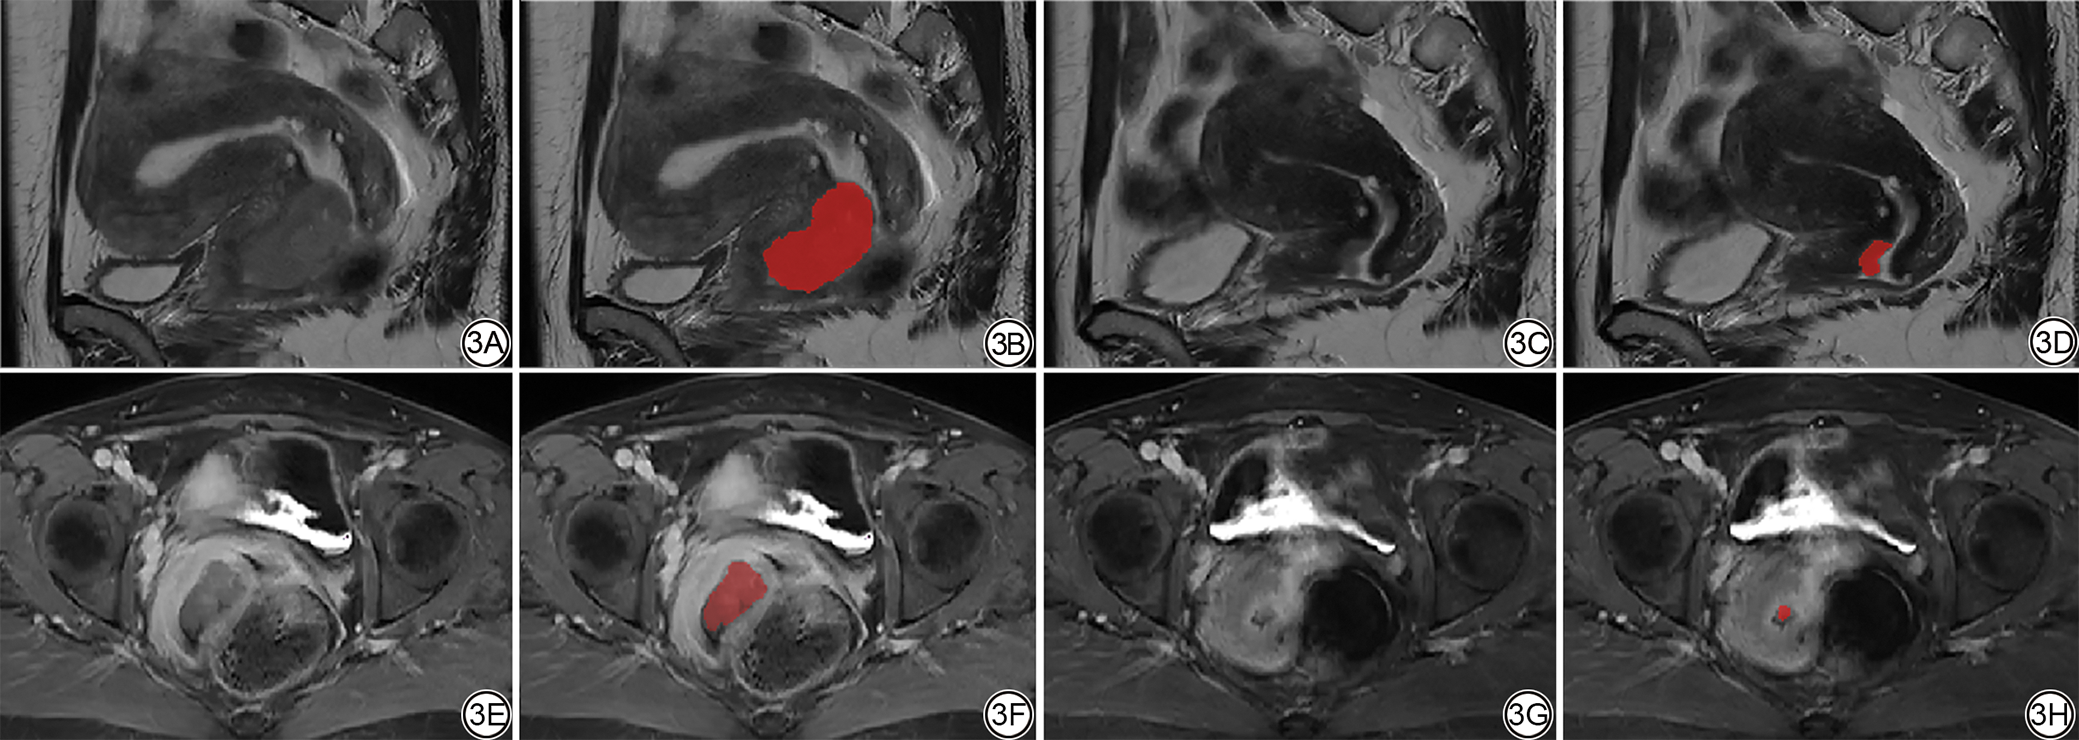

将格式转换后将图像导入ITK-SNAP3.8(版本4.2.0,http://www.itksnap.org)软件,由一位具有3年经验的放射科住院医师参考所有序列图像,在Sag_T2WI和Ax_T1CE序列上沿肿瘤轮廓在所有连续层面上逐层勾画感兴趣区(region of interest, ROI)(图2图3),然后由具有二十多年经验的放射科主任医师进行审查,对有争议的ROI进行协商并达成一致。

图3  女,49岁,低风险组。3A、3B:NACT前Sag_T2WI序列图像;3C、3D:NACT后Sag_T2WI序列图像;3E、3F:NACT前Ax_T1CE序列图像;3G、3H:NACT后Ax_T1CE序列图像。NACT:新辅助化疗;Sag_T2WI:矢状位T2加权成像;Ax_T1CE:轴位对比增强T1加权成像。

Fig. 3  Female, 49 years old, low-risk group. 3A, 3B: Sag_T2WI images before NACT; 3C, 3D: Sag_T2WI images after NACT. 3E, 3F: Ax_T1CE images before NACT. 3G, 3H: Ax_T1CE images after NACT. NACT: neoadjuvant chemotherapy; Sag_T2WI: sagittal T2-weighted imaging; Ax_T1CE: axial contrast-enhanced T1-weighted imaging.